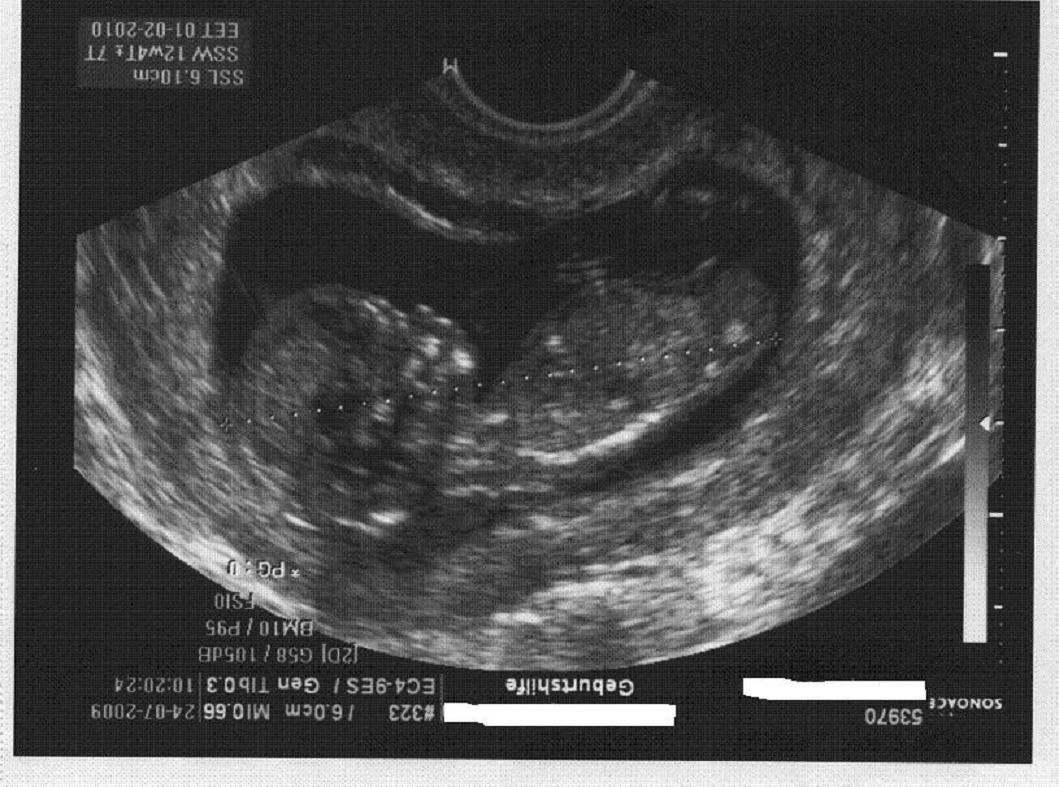

Kaulquappe außer einem Ziehen hin und wieder merk ich noch nix. Und du ?